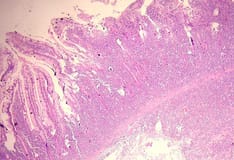

Mixed cellularity Hodgkin lymphoma showing both mononucleate and binucleate Reed-Sternberg cells in a background of inflammatory cells (hematoxylin and eosin, original magnification x200).